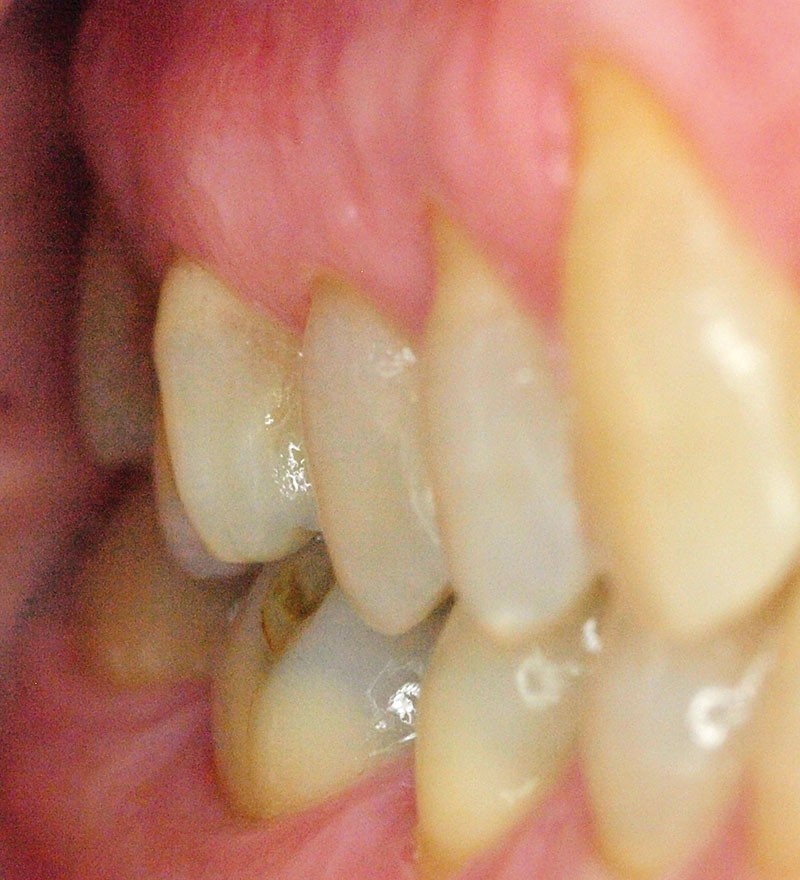

Voilà 6 mois, une patiente se présente à notre cabinet au motif d’une douleur récurrente sur le secteur molaire supérieur droit lors de la mastication. Une anamnèse rapide et cadrée est réalisée pour optimiser le temps passé et avancer les éléments diagnostiques. La patiente décrit une gêne ancienne, déclenchée essentiellement par la mastication. À l’auscultation, les examens endo-buccaux et radiologiques montrent une denture superbe avec très peu de soins, une hygiène buccale sans reproche, et des fonctions manducatrices saines [1] (fig. 1 et 2).

Ce jour-là, aucun diagnostic précis n’est posé concernant cette perception douloureuse. Aussi, nous proposons à la patiente de réévaluer cette sensibilité en fonction de son évolution, et au plus tard sous six mois. Lors de cette consultation de réévaluation, la patiente se présente avec la même doléance, majorée de quelques signes : la douleur, toujours furtive, est plus régulièrement présente, augmentée en puissance (nous n’avons malheureusement pas noté d’échelle d’évaluation douloureuse comparative), mais également déclenchée par la pression dento-dentaire (sans présence d’aliment). En complément, la patiente confirme que cette douleur est plus importante lors de la dépression, du relâché de l’occlusion que lors de la pression [2]. Comme six mois auparavant, la patiente présente un bon état de santé général, n’a ni rhume ni sinusite. L’anamnèse est donc complétée et, grâce à un protocole rigoureux [3], elle nous permet de découvrir aussi des céphalées, des douleurs musculaires et cervicales récurrentes malgré l’intervention d’un ostéopathe. En poussant plus loin l’échange, la patiente déclare une très importante période de stress depuis neuf mois, et nous mettons en évidence une attitude de contacts…